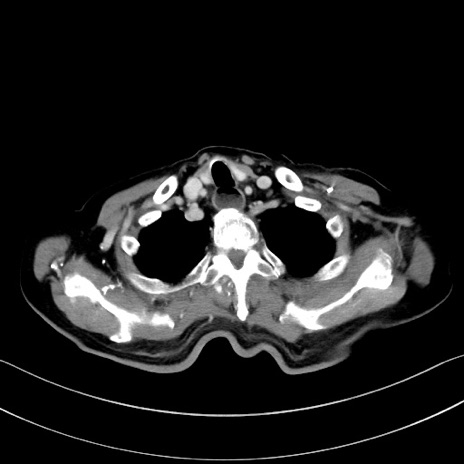

症例28(横断像)

【症例】60歳代男性

【主訴】嘔吐

【現病歴】胃癌にて胃全摘後。食思不振が悪化し、夜中に嘔吐することがある。

【既往歴】胃癌、胃全摘、脾摘、胆摘後

【データ】WBC 5900、CRP 10.56